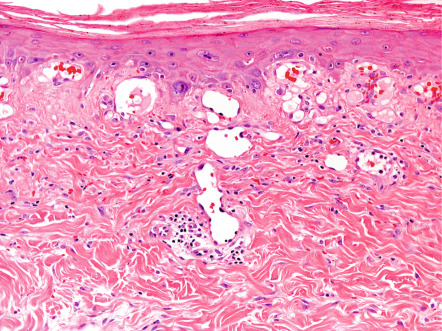

The earliest histopathologic changes include epidermal atrophy, vasodilation, and dermal pigmentation (both melanin and hemosiderin) ( Fig. 88.4 ). As lesions progress, the epidermal atrophy becomes more pronounced, with flattening of the rete ridges. Focal hyperkeratosis and dyskeratosis are noted along with squamous atypia. Basal cell vacuolization has been reported and the dermal–epidermal junction may exhibit interface dermatitis. The dermis appears thinned and sometimes edematous, with accumulation of abnormal elastic tissue and pigment as well as ectatic capillaries. Dermal capillaries may exhibit enlarged endothelial cells with hyperchromatic nuclei. Later lesions may also show basophilic degeneration of connective tissue. Hemosiderin deposition and prominent telangiectasias are seen most often in leg lesions. Ultrastructural evaluation also shows increased melanocyte dendritic processes, suggesting melanocyte activation .